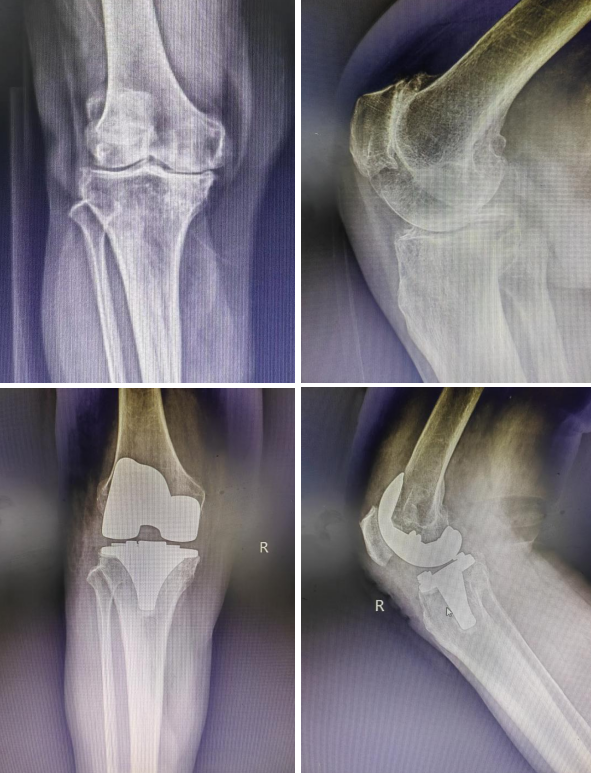

患者张女士,永州江华县人,右膝关节疼痛多年,走路活动严重受限,曾到多家医院就诊治疗,效果不佳。今年6月,曹旭博士入驻江华县人民医院后,对张女士进行仔细的体格检查和影像学资料的复习。在完善了术前准备后,于今年6月底为患者实施了右侧全膝关节置换术。手术过程十分顺利,患者术后第二天就可下床在助行器的帮助下行走。张女士和家人术后表示,现在遇上了一个好时代,国家带来这么好的福利,又遇上湘雅三医院专家帮扶,真的是太幸运了。

上,术前X片提示患者右膝关节严重磨损

下,术后X片,患者膝关节假体位置良好